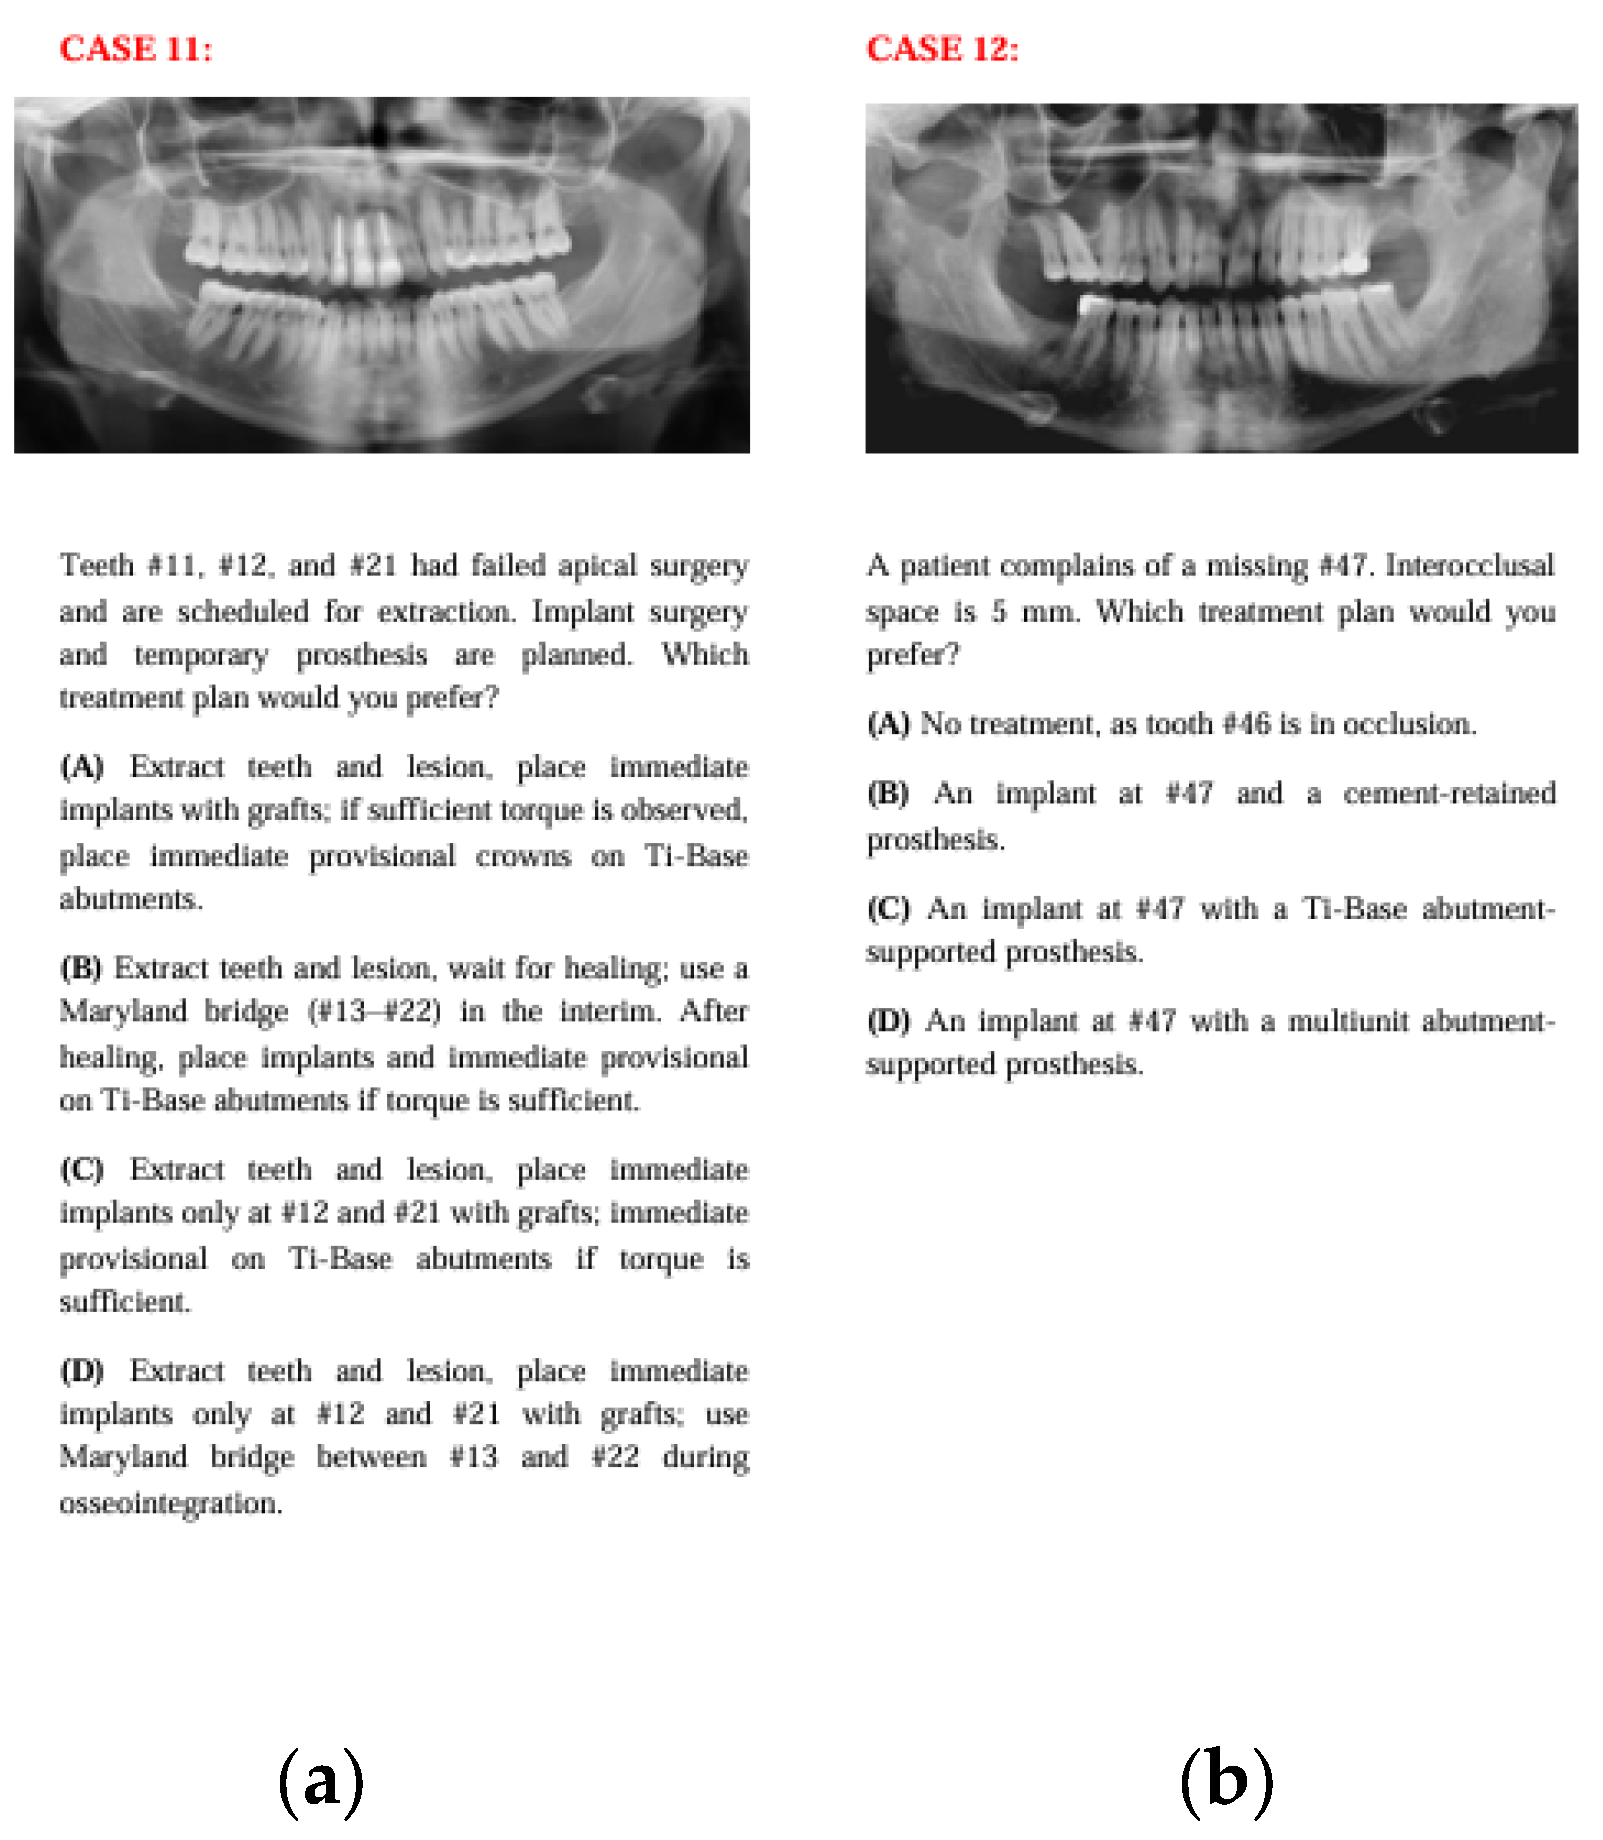

Figure 3. The panoramic radiographs, descriptions, and four treatment options of Case 5 (a) and Case 6 (b).

In Case 11, where the case involved anterior esthetics and immediate implantation, clinicians predominantly chose options C and D, while AI chose option A. This may be because clinicians aimed to avoid the risk of placing implants across the entire area in an anterior region with a history of lesions or, guided by clinical intuition, leaned toward treatments with fewer implants or plans like option D that involve waiting for osseointegration to reduce complications. AI, on the other hand, may have leaned toward option A, which aligns with the current literature emphasizing the success of immediate implantation with immediate provisional prostheses in the esthetic zone, aiming to place as many implants as possible.

In Case 12, although option C was the most preferred across all groups, a significant distribution difference was found between human and artificial intelligence. In this question evaluating abutment types in single-implant restorations, clinicians, based on varied clinical experiences, opted for different choices, whereas AI consistently preferred single crown restorations on Ti-base abutments, which are frequently highlighted in the recent literature.